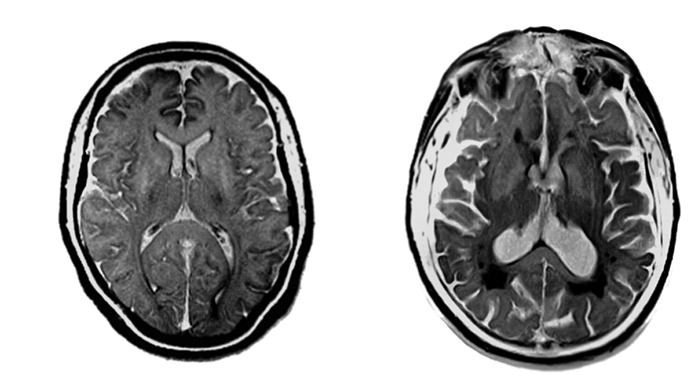

Das Gehirn ohne und mit alzheimertypischen Veränderungen